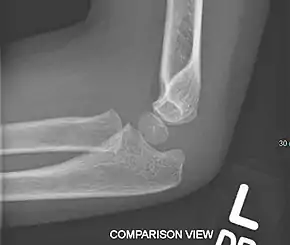

Normal elbow in same child, other side